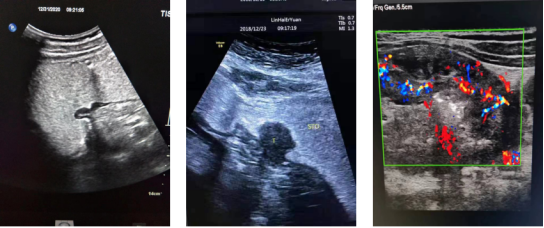

超声胃病声像图,依次为胃溃疡、胃癌、晚期胃癌▲